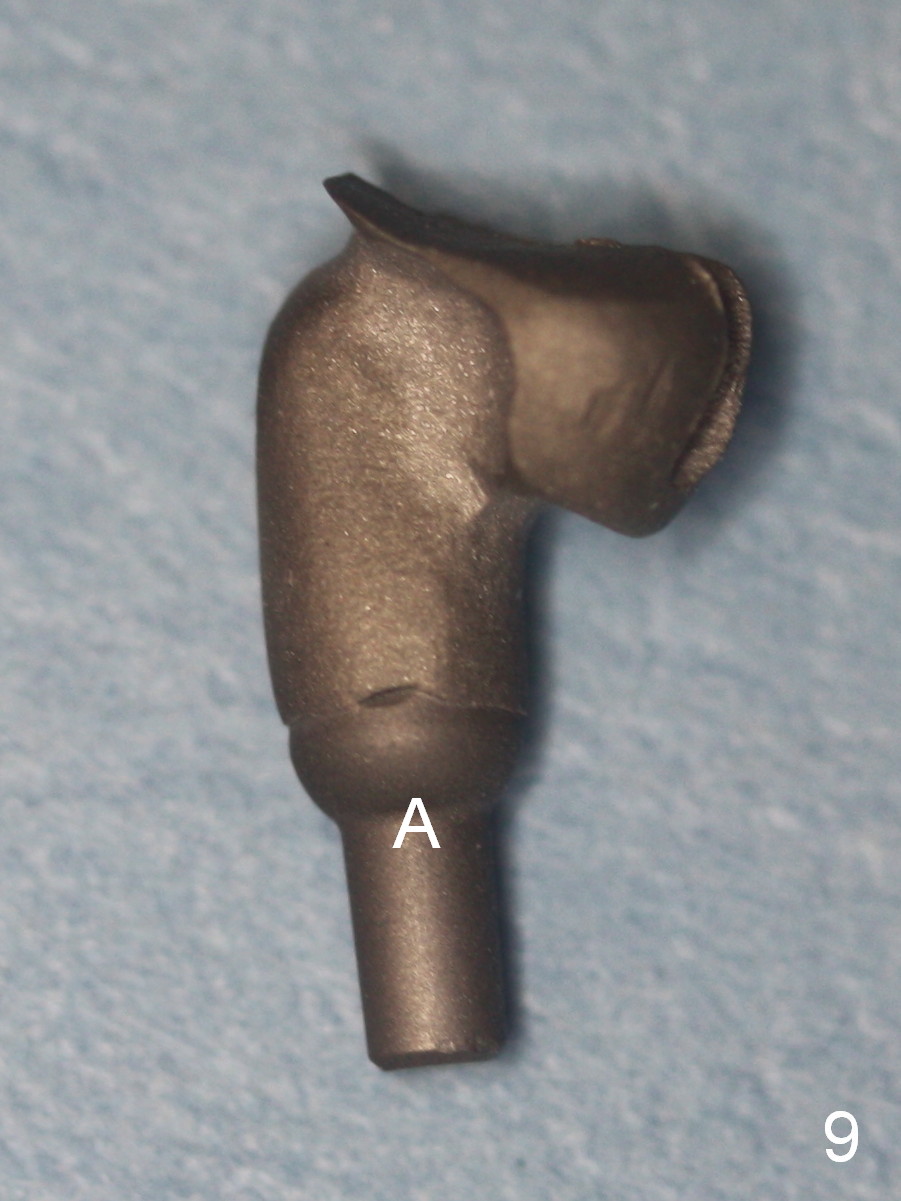

A 68-year-old man has pain and swelling associated with the tooth #5 (Fig.1). The fistula (*) is connected to the periapical radiolucency using a gutta percha (Fig.2 <). There are deep pockets distobuccal and lingual. The lingual root is found to have oblique fracture upon extraction. The distobuccal plate perforates (Fig.3). Collagen plug is placed. The buccal plate is concave (Fig.4) and socket density is low 2.5 months post extraction. Three months post extraction a 4.5x8 mm Bicon implant is placed after reamer and osteotome osteotomy (Fig.6). Bone density around the implant appears to increase 5 months post placement (Fig.7). Porcelain-fused-to-metal crown is cemented 2 weeks later. Bucco-occlusal porcelain chips 2 months post cementation. The patient decides to redo the crown. PA is taken before crown removal (Fig.8: 3 year 10 months post cementation). When a straight abutment is removed (Fig.9 A), a 15° angled abutment has to be used (Fig.10 red) for restoration.